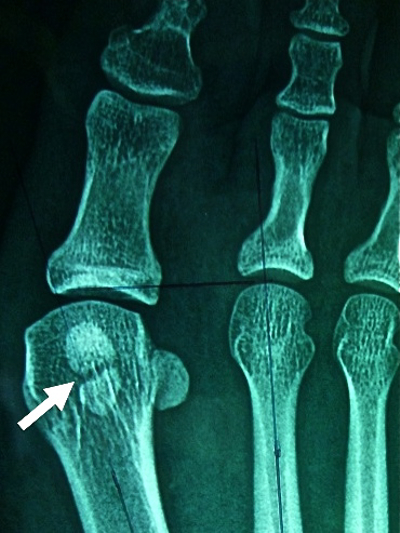

atrophie du sésamoïde externe |